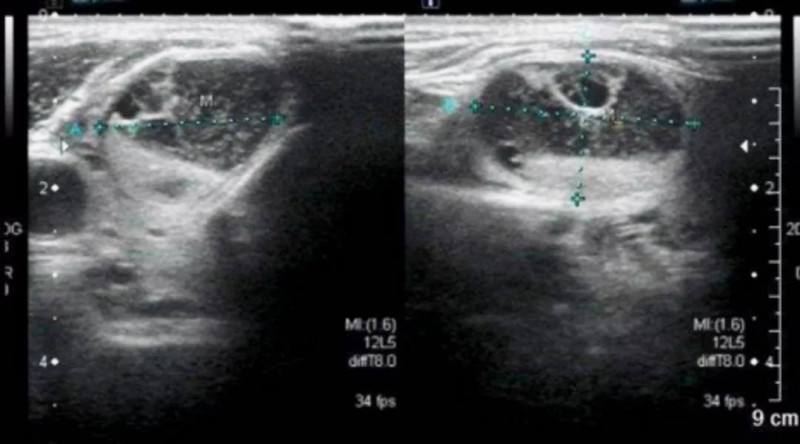

医生通常会收集患者的完整病史,并对甲状腺及附近的颈部淋巴结做详细检查。甲状腺B超是最常用的检查手段,因为甲状腺这样比较浅表的器官,可以检查出直径仅为2毫米的微小结节,并清晰地看到其大小、形态、境界和位置,还可提示结节是否有钙化、血流状况如何。

超声检测中,如提示结节边界清晰整齐,无回声,后方回声增强,内部可见少许血流,内部未见钙化灶等表现,多为良性甲状腺结节。如提示边界不清楚,边缘整齐差,实性结节,内部可见砂粒样钙化,后方回声衰减,结节纵横比失常,锁骨上下淋巴结肿大,中央髓质回声消失等表现,则多是恶性甲状腺结节。此外,甲状腺恶性病变多为单发结节,而甲状腺良性病变则多是多发结节。

不过,因为超声属于影像诊断,各种超声的影像学图像的特异性和敏感性存在较大的差异。因此在采用超声对甲状腺结节进行鉴别诊断的同时,还需要结合其他的检查诊断结果,有恶性的可能时,应做进一步的颈部CT或磁共振检查,甚至进行细针穿刺抽吸活检,明确诊断。